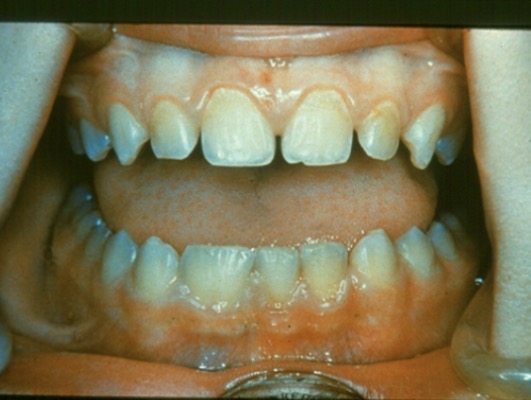

What is this condition?

Supernumerary teeth